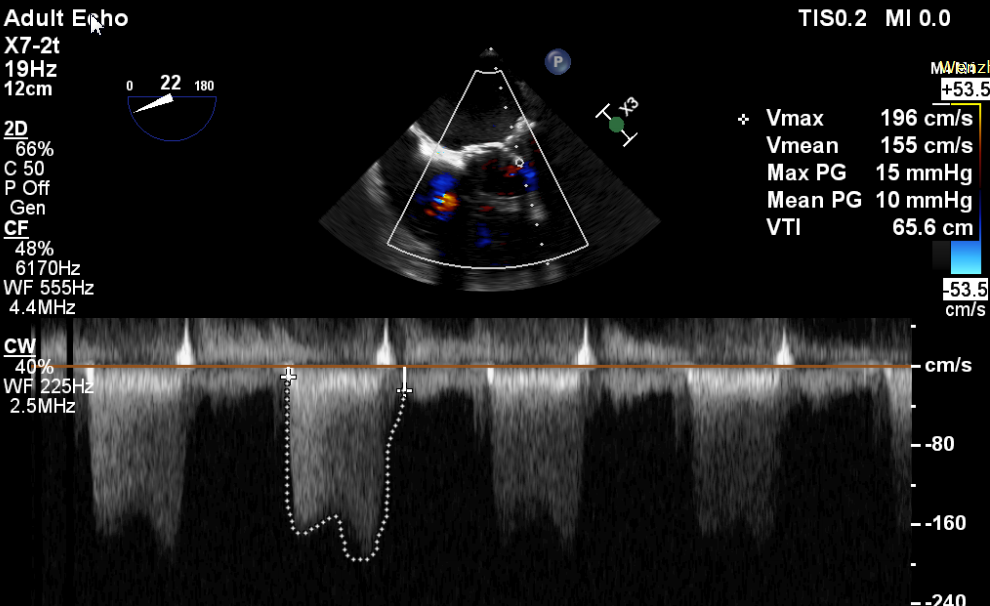

患者,男,70岁,于1月前无明显诱因下出现活动后胸闷,步行100米后出现气促伴双下肢乏力,无胸痛、发热、头晕头痛、发热畏寒、恶心呕吐及咳嗽等不适。患者于7年前行二尖瓣生物瓣置换术(Edwards Perimount 27#)。术前心脏超声提示:二尖瓣生物瓣置换术后:生物瓣重度狭窄(有效瓣口面积0.58cm²,MPG=12mmHg);左房增大(57mm)左室增大(舒张末前后径73mm),左室壁静息状态下运动弥漫性减弱,左室收缩功能明显减低(EF=29%,Simpson法);轻度肺动脉高压;术前心功能IV级。

CDFI提示过瓣血流通畅